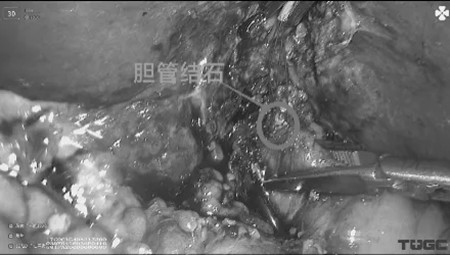

手术如期顺利进行,解剖胆囊三角后,充分显露胆囊管及胆总管前壁,用一次性结扎夹将胆囊壶腹部夹闭,施行胆囊管T字切开,用超细胆道镜经胆囊管行胆总管探查,发现胆总管下段多发结石,用取石网篮抓取,并从胆囊管取出,胆道镜探查无结石残留。随后用结扎夹双重夹闭胆囊管,常规切除胆囊。

图二超细胆道镜经胆囊管胆道探查

图三经胆囊管取石